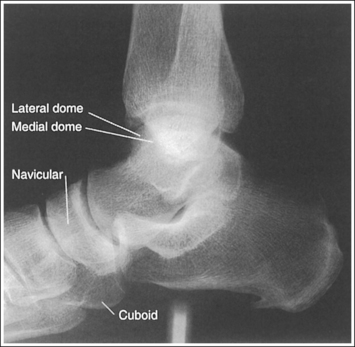

The foot is in a lateral projection. The talar domes are superimposed, the tibiotalar joint is open, and the distal fibula is superimposed by the posterior half of the distal tibia.

• Talar domes. The domes of the talus are formed by the most medial and lateral aspects of the talar's trochlear surface. On a lateral foot projection, they appear as domed structures that articulate with the tibia. On a properly positioned lateral foot projection, the talar domes should be superimposed and appear as one and the tibiotalar joint should be open. When the lateral foot is mispositioned, the domes are individually demonstrated, and they obscure the tibiotalar joint. Proximal-distal misalignment of the domes results from poor knee and lower leg positioning, and AP misalignment of the domes results from poor foot positioning.

When viewing a lateral foot projection that demonstrates one of the talar domes proximal to the other, evaluate the height of the longitudinal arch and the degree of narrowing or widening of the talocalcaneal joint to determine which dome is the proximal dome. If the navicular bone is superimposed over more of the cuboid than expected and the talocalcaneal joint is narrowed, the lateral dome is the proximal dome; if the navicular bone is superimposed over less of the cuboid than expected and the talocalcaneal joint is wider, the medial dome is the proximal dome.

• Effect of foot positioning on AP talar dome superimposition. To demonstrate accurate AP alignment of the talar domes, position the lateral surface of the foot parallel with the IR. If this surface is not parallel with the IR, one of the talar domes is demonstrated anterior to the other. When the leg is rotated more than needed to place the lateral foot surface parallel with the IR, as shown in Figure 6-29, the medial talar dome is demonstrated anterior to the lateral talar dome (see Image 20). If the leg is not rotated enough to place the lateral foot surface parallel with the IR, as shown in Figure 6-30, the medial talar dome is demonstrated posterior to the lateral talar dome (see Image 21).

When viewing a lateral foot projection that demonstrates one of the talar domes anterior to the other, evaluate the position of the fibula in relation to the tibia to determine how to reposition the patient. On most lateral foot projections with accurate positioning, the fibula is positioned in the posterior half of the tibia. If the fibula is demonstrated more posteriorly than this relationship on a lateral foot projection with poor positioning, the medial talar dome is anterior and the patient was positioned with the forefoot depressed and the heel elevated (leg externally rotated), as shown in Figure 6-29. If the fibula is demonstrated more anteriorly than this relationship, the medial talar dome is posterior and the patient was positioned with the forefoot elevated and the heel depressed (leg internal rotation), as shown in Figure 6-30.